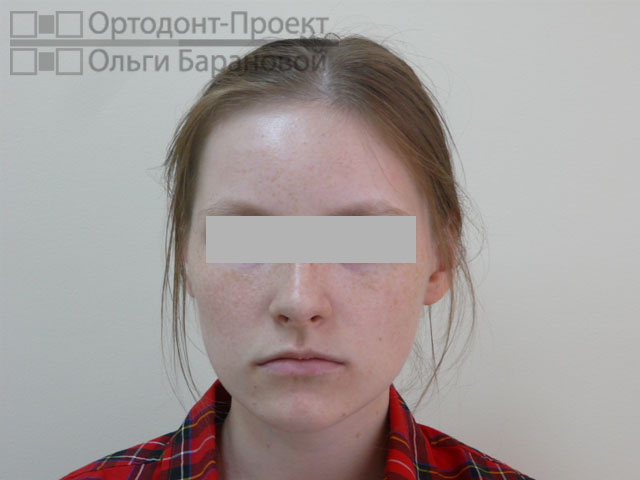

Проблема: к ортодонту О.А. Барановой обратилась молодая девушка с жалобами на то, что криво растут зубы.

Решение: выполнено лечение с удалением зубов, наиболее эффективное в данном случае. Для лечения использованы металлические брекеты Damon.

Ортодонт О.А. Баранова провела осмотр и рассказала о возможностях ортодонтического лечения. Возможны два варианта лечения при скученности зубов – с удалением или без удаления зубов. В «ОРТОДОНТ-ПРОЕКТЕ Ольги Барановой» редко используется удаление зубов, но в данном случае, при сильной скученности зубов и тонком биотипе пародонтальных тканей, у девушки ещё есть полноценные «восьмерки», поэтому все признаки за лечение с удалением. В данном случае лечение с удалением зубов приведёт к максимально грамотному, эстетичному и стабильному результату.

Фотометрия перед ортодонтическим лечением:

Диагноз ортодонта: скученность фронтальной группы зубов верхней и нижней челюсти, сужение и укорочение верхнего и нижнего зубных рядов. Окклюзия нормальная.